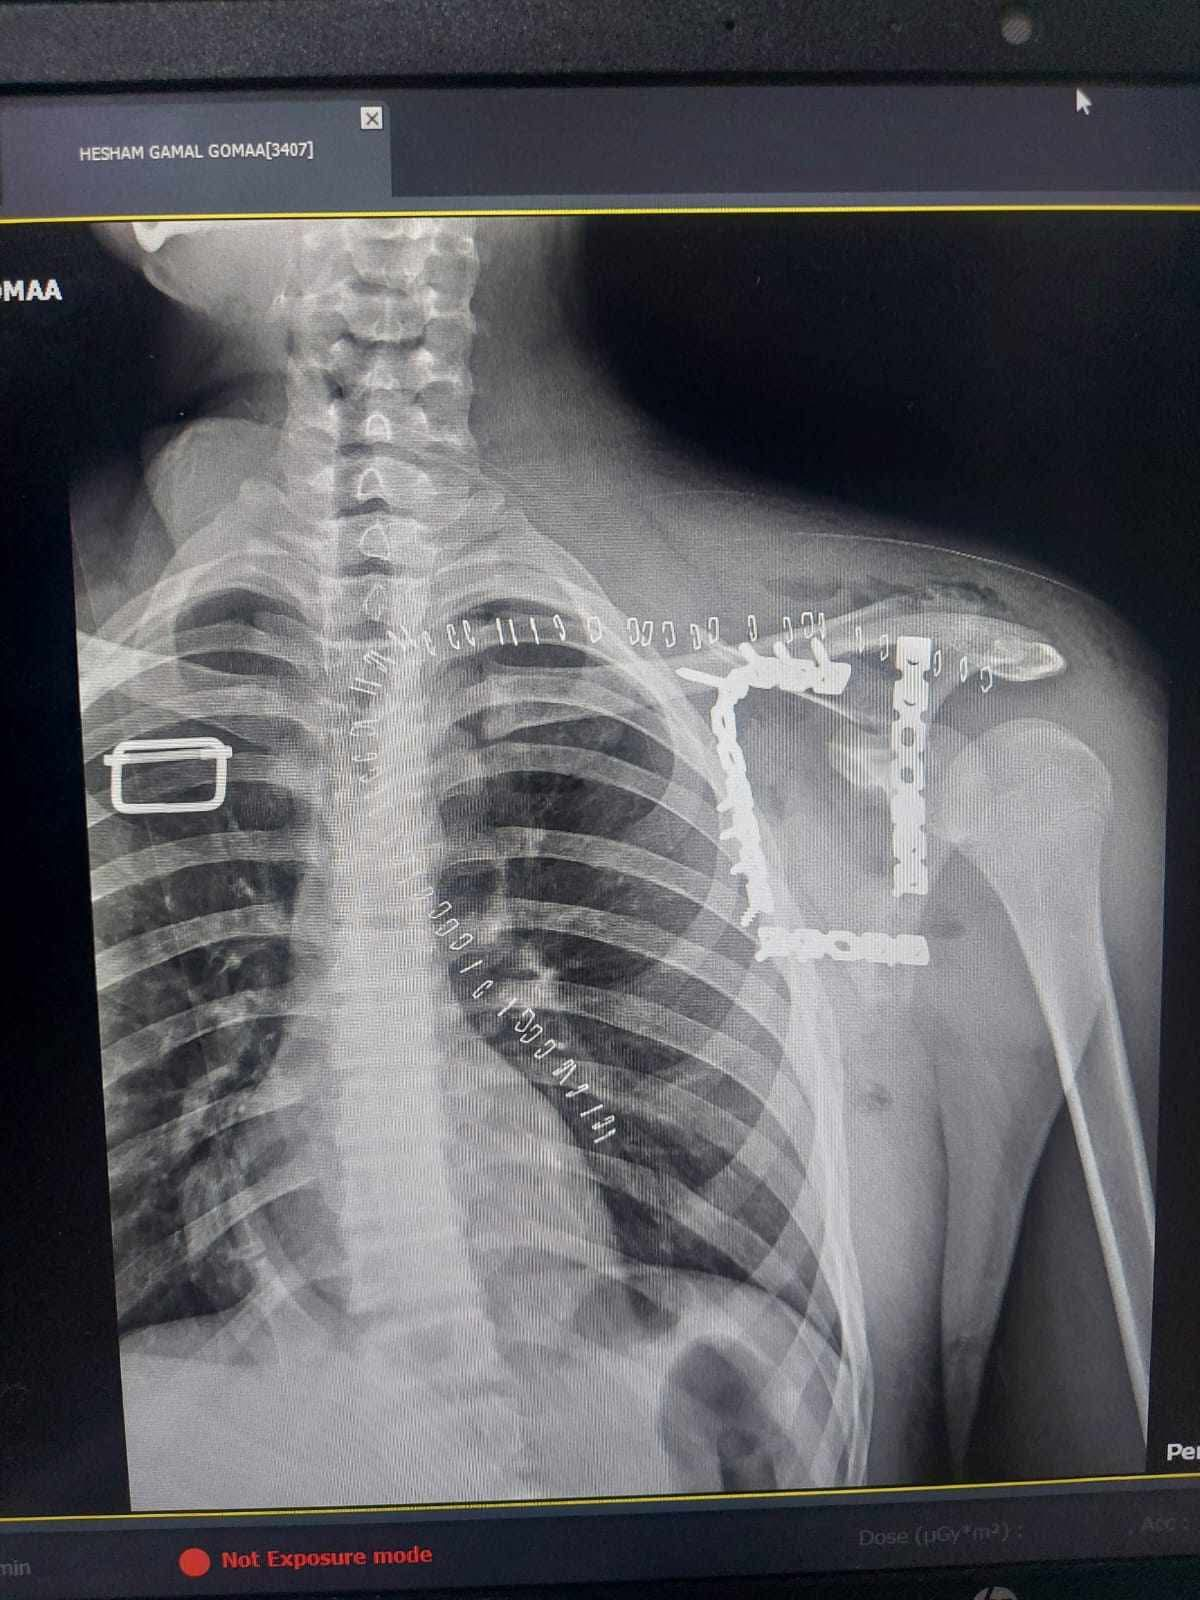

شهد مستشفى التأمين الصحي بالفيوم واقعة طبية متميزة بعد استقبال شاب يبلغ من العمر 17 عاما كان يعاني من كسر مفتت بعظمة لوح الكتف وهي من الاصابات الدقيقة والنادرة التي تحتاج الى تدخل جراحي متخصص نظرا لتعقيد موقعها وتشابكها مع العضلات والمفاصل المحيطة ما يجعل التعامل معها تحديا كبيرا امام الفرق الطبية.

خضع المريض لعملية جراحية معقدة استمرت نحو 4 ساعات تحت تأثير التخدير العام حيث قام الفريق الطبي برد وتثبيت الكسر باستخدام الشرائح والمسامير في اجراء دقيق يتطلب مهارة عالية وخبرة كبيرة خاصة في هذا النوع من الاصابات النادرة.

العملية مرت بنجاح دون حدوث مضاعفات وتمكن الاطباء من تثبيت العظمة بشكل سليم يساعد على استعادة المريض لوظائف الكتف تدريجيا خلال فترة العلاج.